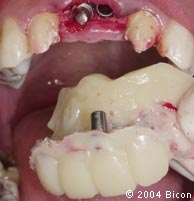

41. | 取全牙弓的印模。 |